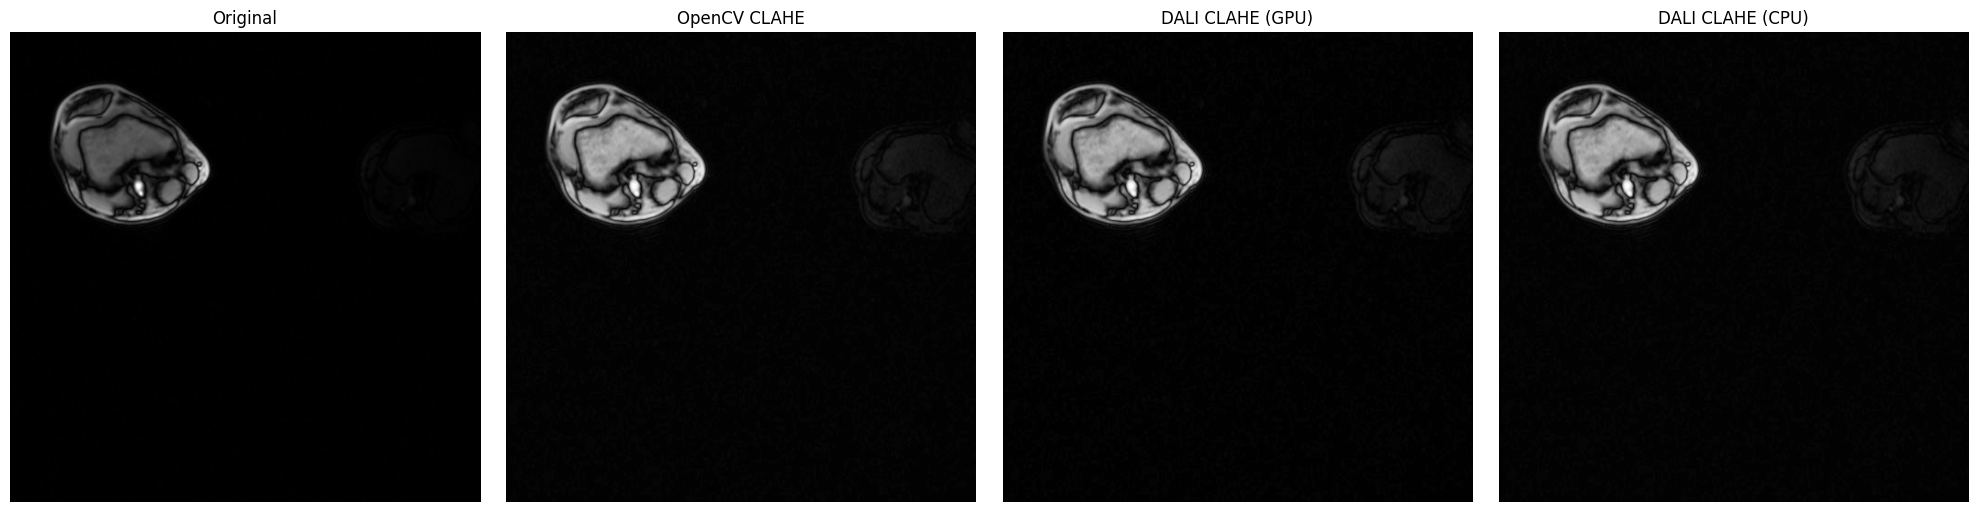

DALI CLAHE vs OpenCV CLAHE on Medical Imaging (Knee MRI)#

This section demonstrates CLAHE on real low-contrast medical imaging data - knee MRI slices from the DALI_extra repository. Medical imaging is where CLAHE truly shines, as these images often have naturally low contrast that benefits significantly from adaptive histogram equalization.

The knee MRI slices (db/3D/MRI/Knee/npy_2d_slices/STU00001/SER00001/) are perfect for demonstrating CLAHE because:

• Low local contrast: MRI data typically has subtle tissue boundaries

• Grayscale: Single-channel data ideal for CLAHE

• Real-world clinical data: Demonstrates practical medical imaging applications

• Multiple sequences: 15 different series (SER00001-SER00015) available for experimentation

fig, axes = plt.subplots(1, 4, figsize=(20, 5))

axes[0].imshow(mri_array.squeeze(), cmap="gray")

axes[0].set_title("Original")

axes[0].axis("off")

axes[1].imshow(opencv_result.squeeze(), cmap="gray")

axes[1].set_title("OpenCV CLAHE")

axes[1].axis("off")

axes[2].imshow(dali_gpu_flat, cmap="gray")

axes[2].set_title("DALI CLAHE (GPU)")

axes[2].axis("off")

axes[3].imshow(dali_cpu_flat, cmap="gray")

axes[3].set_title("DALI CLAHE (CPU)")

axes[3].axis("off")

plt.tight_layout()

plt.show()

print("\nImplementation Comparison Metrics:")

print("=" * 60)

print(f"OpenCV vs DALI GPU:  MSE = {mse_ocv_gpu:.4f}, MAE = {mae_ocv_gpu:.4f}")

print(f"OpenCV vs DALI CPU:  MSE = {mse_ocv_cpu:.4f}, MAE = {mae_ocv_cpu:.4f}")

print(f"DALI GPU vs CPU:     MSE = {mse_gpu_cpu:.4f}, MAE = {mae_gpu_cpu:.4f}")

print("\nNote: Lower values indicate closer agreement between implementations.")

../../../_images/examples_image_processing_clahe_dynamic_mode_11_0.png